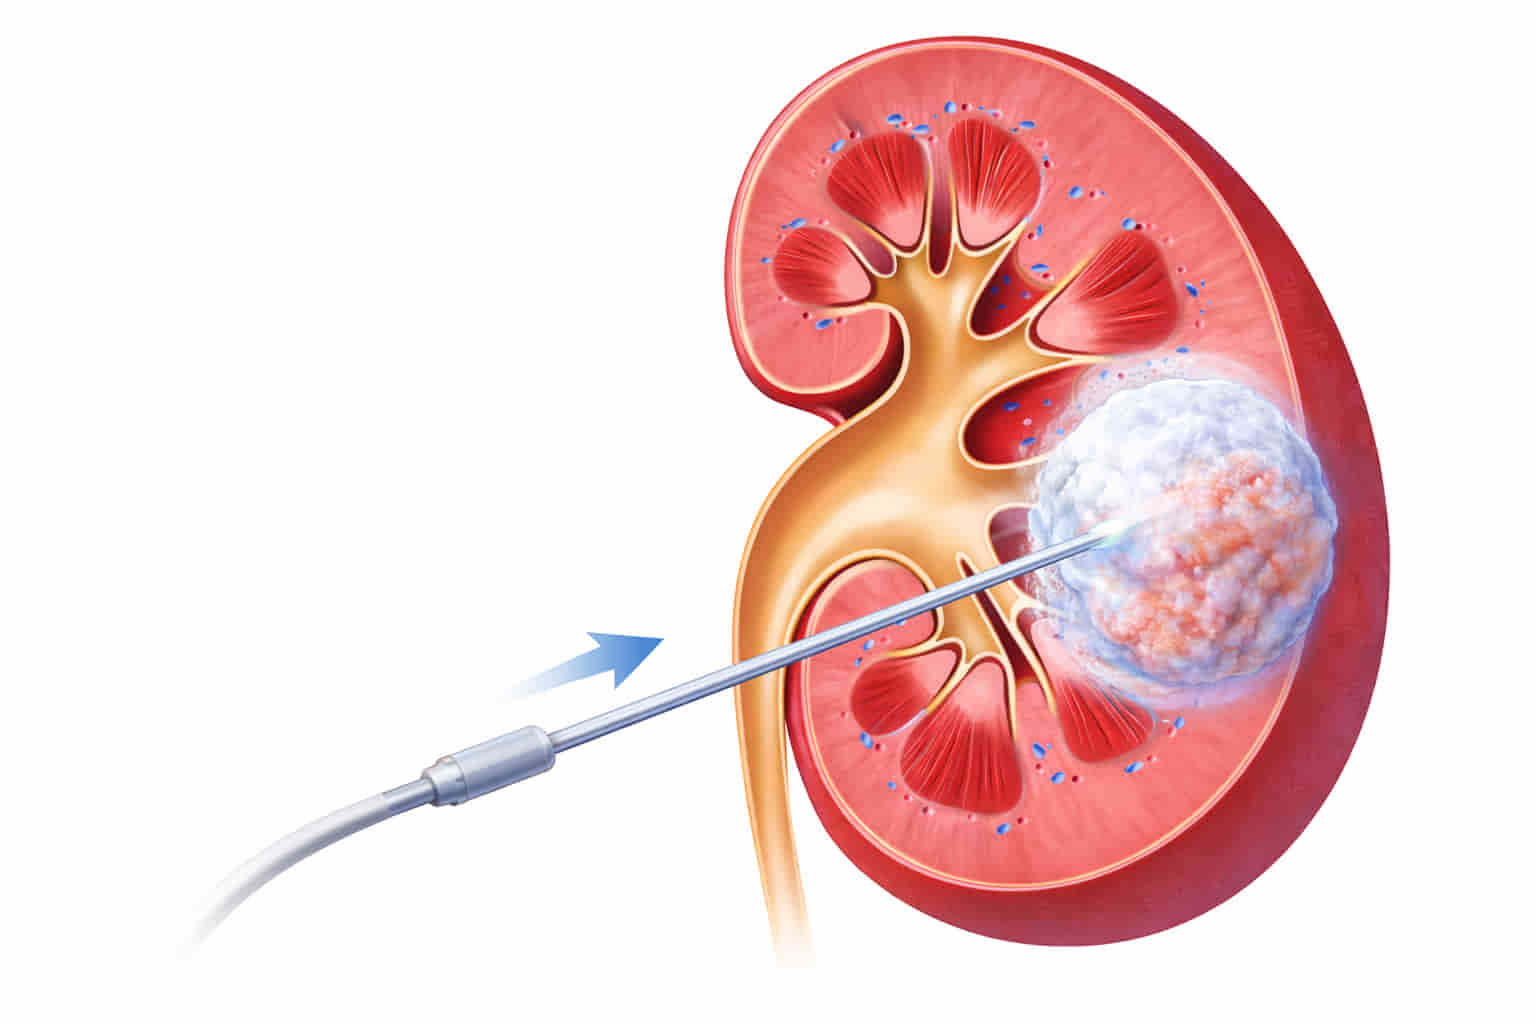

1. How it Works

The "Pinhole" Access: An interventional radiologist uses live imaging (like a CT scan or ultrasound) to guide one or more thin, needle-like probes through the skin directly into the tumor.

The Freezing Cycle: Argon gas is circulated through the needles, creating an "ice ball" that reaches temperatures as low as -180°C. This extreme cold ruptures the cancer cells, destroying the tumor while it remains inside the body.

Natural Healing: After the procedure, the needles are removed and the body naturally absorbs the dead tumor tissue over time, leaving only a small amount of scar tissue.

The actual freezing process takes about 30 to 45 minutes, but the total time in the procedure room—including setup and imaging—is usually around 2 hours.

❓ What happens to the tumor after it is frozen?

The dead cancer cells remain in the kidney but are no longer active. Over several months, your body’s immune system naturally breaks down the dead tissue and replaces it with a small, harmless scar.

❓ Will I have a scar?

No. The cryoprobes are about the size of a standard needle. There are no incisions to stitch; we simply place a small adhesive bandage over the entry points.